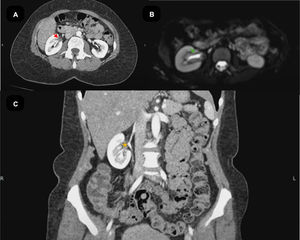

During the course of the disease, the patient developed abdominal pain. A contrast-enhanced abdominal CT scan revealed irregular thickening of the renal pelvis walls and the proximal right ureter. Serial urinary cytology ruled out associated neoplastic pathology (Fig. 4). Given the extensive organ involvement, the risk of renal injury, and the potential for organ dysfunction, treatment with Rituximab 1g dose was initiated on days 0 and 15 [9].

Abdominal magnetic resonance imaging (MRI) and computed tomography (CT). (A) Contrast-enhanced computed tomography (CT), axial view, demonstrating thickening of the right ureteral wall with enhancement (red arrow). (B) Magnetic resonance imaging (MRI), diffusion-weighted imaging (DWI) sequence, axial view, showing signal restriction consistent with active inflammation and tissue infiltration of the right ureter (green arrow). (C) Contrast-enhanced computed tomography (CT), coronal view, revealing mild hydronephrosis due to dilation of the right renal pelvis (orange asterisk).

The patient does not meet any exclusion criteria and, according to ACR/EULAR classification criteria, scores 35 points, confirming the diagnosis of IgG4-RD. Concurrently, based on Okazaki's criteria, the patient fulfills all three diagnostic components: submandibular lymphadenopathy, sialadenitis, dacryoadenitis, and IgG4-related renal disease, evidenced by a hypertrophic lesion affecting the renal pelvis wall and ureter, with no other associated cause [12], an IgG4 1271mg/dL and finally, histopathological analysis revealed over 100 IgG4-positive plasma cells, with an IgG4/IgG ratio greater than 0.4, supporting the diagnosis of IgG4-RD.